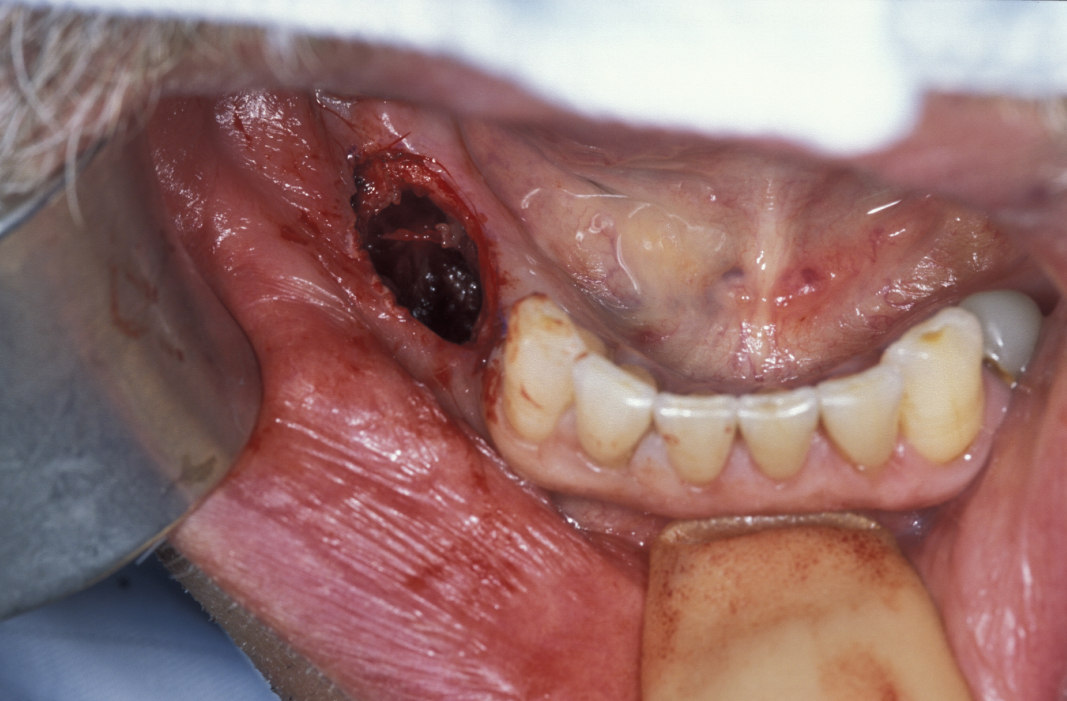

Limited resection represents a more aggressive form of removal of a cyst in that it will include the removal of bone in the vicinity of the cyst (a modified enucleation). It may also be a rim resection of the mandible (where a considerable portion of the mandibular bone is removed but a thin rim of the mandible is preserved to provide continuity of the bone). Treatment with Carnoy’s solution (a mixture of 60% alcohol, 30% chloroform and 10% concentrated acetic acid; applied locally directly after enucleation of a keratocyst) is popular with some surgeons. This is a way to reduce recurrence of keratocysts: the epithelial lining in keratocysts is very friable and therefore difficult to remove completely. Cryotherapy (local use of low temperature) may also have a role. A resection procedure with a reinforcing reconstruction plate is illustrated in Figures 10 to 15.

Figure 12: The involved bone is removed, thus exposing the cyst.

Figure 13: The thick-walled cyst is removed and the surrounding bone is excised.